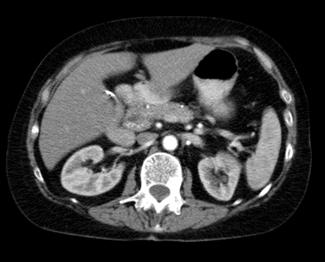

Complicaciones

Hemorragia digestiva baja (masivo)

Megacolon tóxico

♦ Distensión y dolor abdominal

♦ Signos de sepsis (fiebre, taquicardia, hipotensión) y deshidratación

♦ Dilatación del colon (diámetro del colon transverso > 6 cm )

♦ Leucocitosis neutrofílica (> 10,500 / μL) y anemia Perforación → peritonitis

Colitis fulminante: Inflamación severa que causa típicamente > 10 deposiciones por día, sangrado gastrointestinal, dolor y distensión abdominal

Figura 71. Megacolon tóxico. El colon transverso y el colon descendente carecen de rasgos distintivos, con pérdida de las marcas haustrales. El colon transverso está dilatado hasta un diámetro > 6 cm y son visibles algunos pseudopólipos.